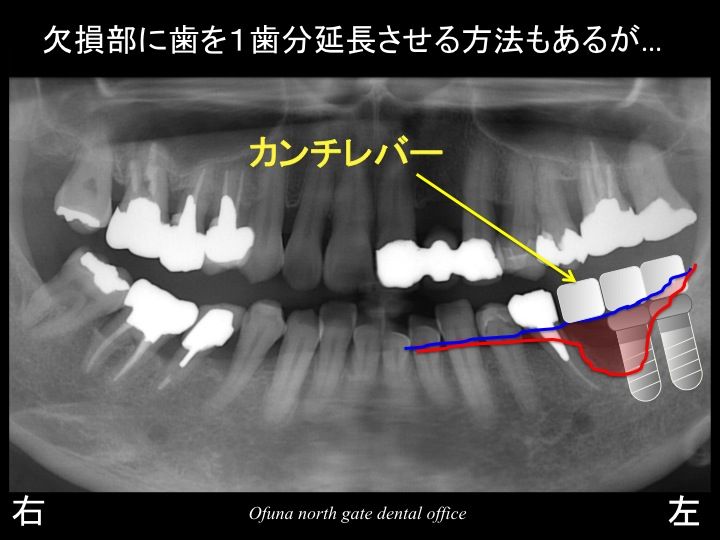

カンチレバー という方法で欠損部をどうにかする方法はあります。

(欠損部(隙間)に歯(被せ物)を1歯分延長させる方法)